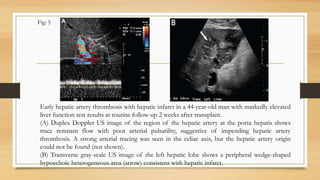

Early hepatic artery thrombosis with hepatic infarct in a 44-year-old man with markedly elevated

liver function test results at routine follow-up 2 weeks after transplant.

(A) Duplex Doppler US image of the region of the hepatic artery at the porta hepatis shows

trace remnant flow with poor arterial pulsatility, suggestive of impending hepatic artery

thrombosis. A strong arterial tracing was seen in the celiac axis, but the hepatic artery origin

could not be found (not shown).

(B) Transverse gray-scale US image of the left hepatic lobe shows a peripheral wedge-shaped

hypoechoic heterogeneous area (arrow) consistent with hepatic infarct.